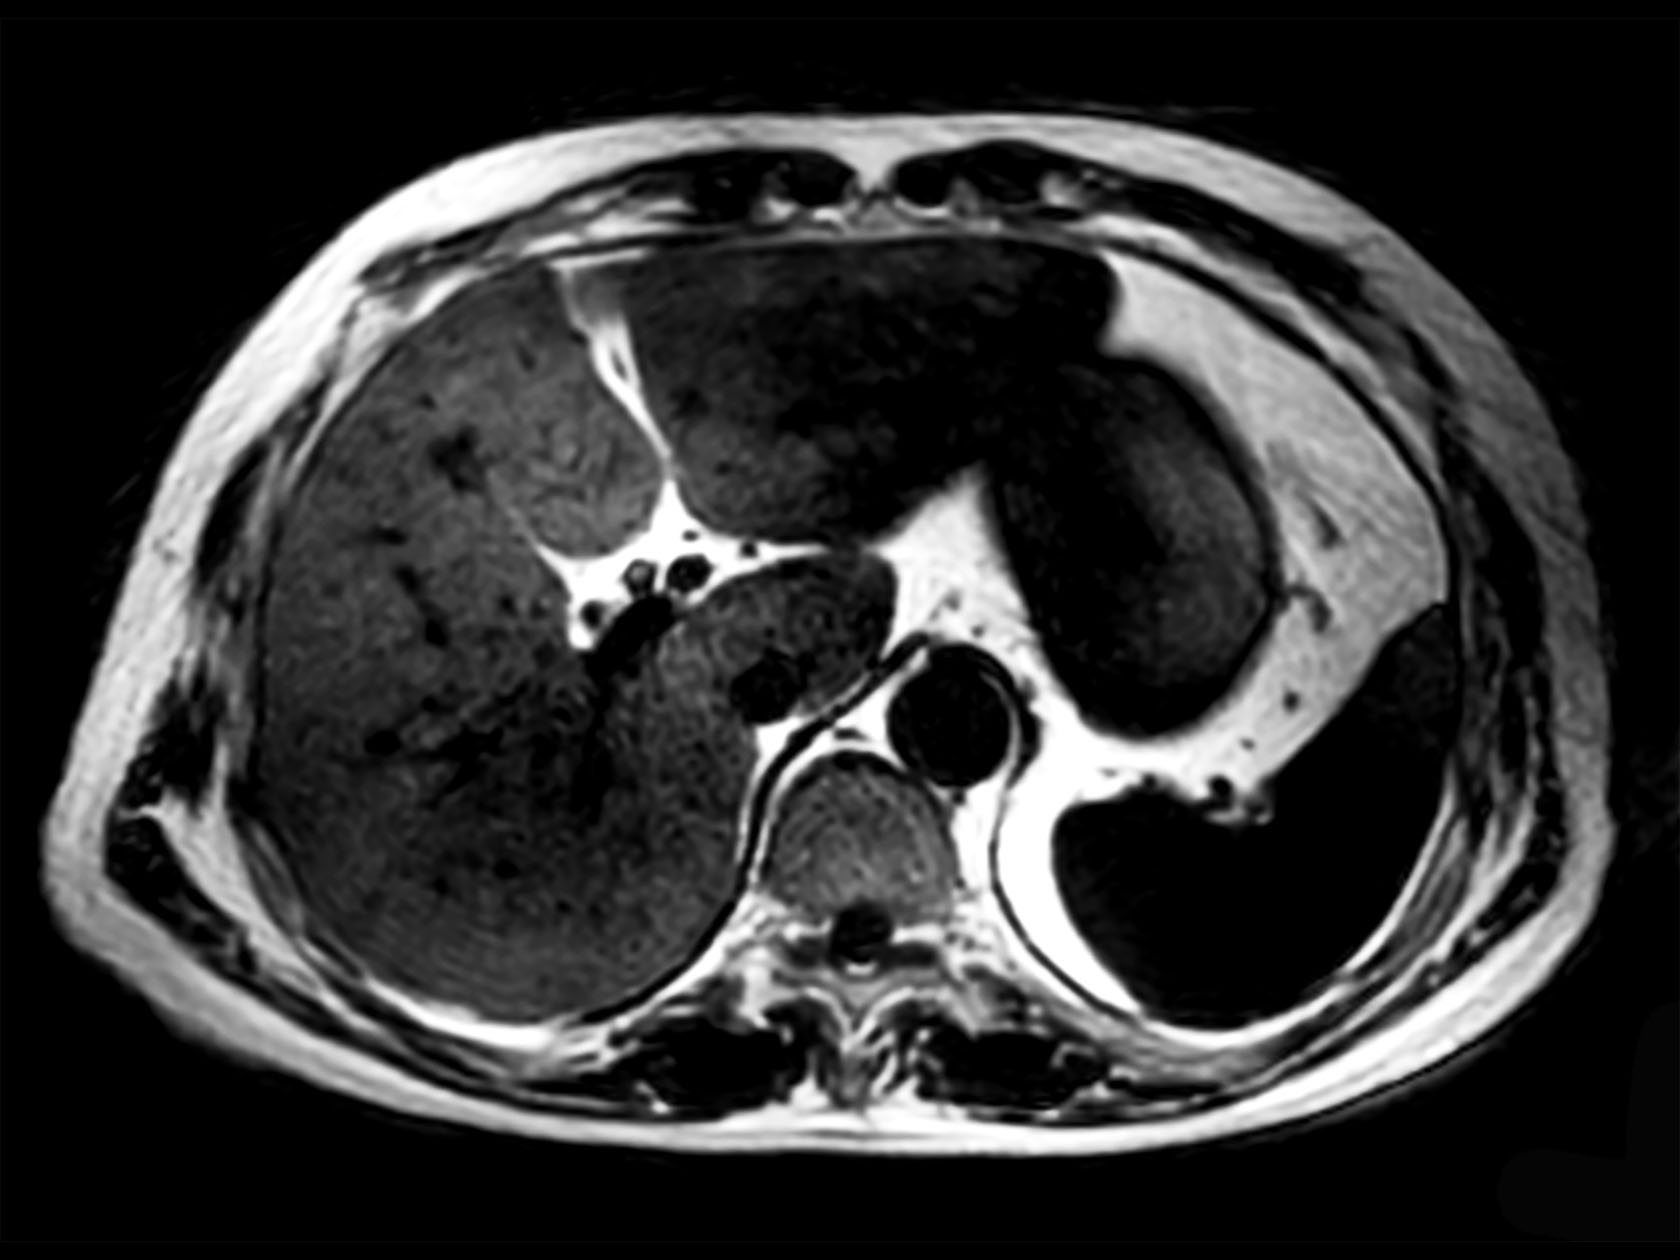

Diffusion (b0)